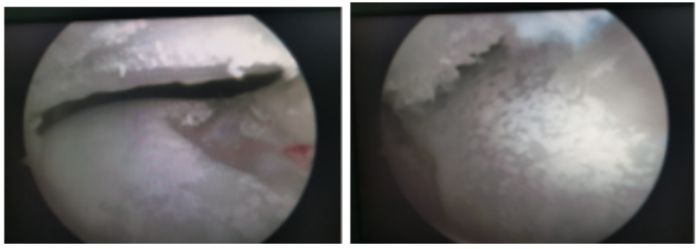

(南华大学附属长沙中心医院)运动医学、关节、骨病科就诊,完善相关检查后,发现他并不是简单的扭伤。后仔细询问病史才发现李先生以前就有尿酸增高的病史,由于一直没有症状,所以就没有引起重视,所以,这次扭伤成了他痛风发作的诱因,目前,李先生已经顺利接受了关节镜术,镜下看到他的软骨上面一层厚厚的“石灰”,经处理伤口恢复良好,关节功能恢复满意。

(关节镜下看到患者的软骨上面一层厚厚的“石灰”)